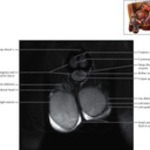

Scrotum and Testes Coronal 4